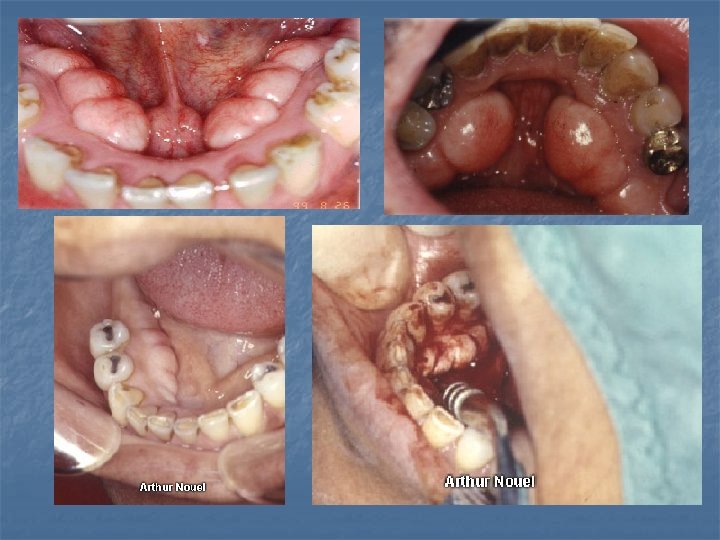

Exostoses n n n Localized boney protuberances that arise from the cortical plate. The best known are the torus palatinus and the torus mandibularis. Most often discovered in adults: Buccal exostoses: a bilateral row of boney hard nodules along the facial aspect of the max and mand alveolar ridge. Palatal exostoses (palatal tubercles) occur along the lingual aspect of max tuberosities. Solitary exostoses; may occur in response to local irritation. May develop beneath free gingival or skin grafts. May see Reactive Subpontine exostosis which may develop from alveolar crest bone

Torus Palatinus n n n A common exostosis that occurs in the palatal vault in the midline. Sometimes classified according to their morphology: Flat torus has a broad base and a smooth surface; Spindle torus has a midline ridge along the palatal raphe; Nodular torus has multiple protuberances that may coalesce forming grooves; Lobular torus has a lobular mass that may arise from a singular base. Most are small (less than 2 cm) but they can increase in size throughout life. They are usually asymptomatic however the overlying mucosa can become irritated secondary to trauma. Most studies show a prevalence of 20 -35% with a female: male ratio of 2: 1. the prevalence peaks during early adult life tapering off in later years showing these are dynamic lesions. Surgical removal is indicated if they become irritated and tramatized or fabrication of a denture base.

Torus Mandibularis n n n A common exostosis that develops along the lingual portion of the mandible. Above the mylohyoid in the premolar region, bilateral in 90% of cases. Can appear on periapical radiographs superimposed over the roots of the teeth. Prevalence 5 -40% depending on the study, more common in Asians and Inuit. Prevalence peaks in early adult life and tapers in later years. It also correlates with bruxism and remaining teeth which supports it’s response to functional stress. Surgery may be needed to accommodate a lower denture.

Stafne Defect n n Asymptomatic radiolucent lesionlocated near the angle of the mandible that represents a concavity of the cortical bone caused by the submandibular gland. It is below the IDN between the molar teeth and the angle of the mandible